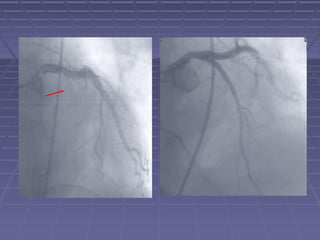

1990’s – Era of “Stent Mania”1990’s – Era of “Stent Mania”

JF

1990’s – Eraof “Stent Mania”1990’s – Era of “Stent Mania”